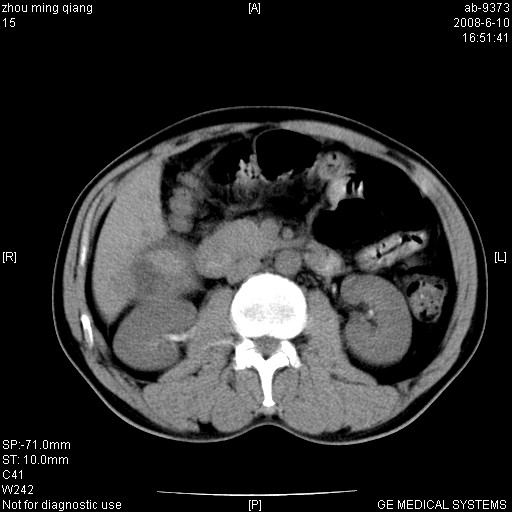

男,49岁.上腹部疼痛、乏力。乙肝表面抗原阳性,afp阳性。

考虑肝右叶巨块型肝癌伴静脉瘤栓形成。

结合临床符合原发性肝癌并出血

灶区见粗大强化动脉影,afp阳性,考虑肝癌;;双肾盂铸形高密度影是什麽???

灶区见粗大强化动脉影,afp阳性,考虑肝癌;;双肾盂铸形高密度影是结石

肝右叶肝癌(部分外生)并出血。

支持肝右叶肝癌并灶内出血,但对于有战友考虑的双肾内高密度影应该是皮试造影剂浓聚所致,而不是结石影;否则增强时静脉期肾盂内高密度造影剂应该有充缺才是。